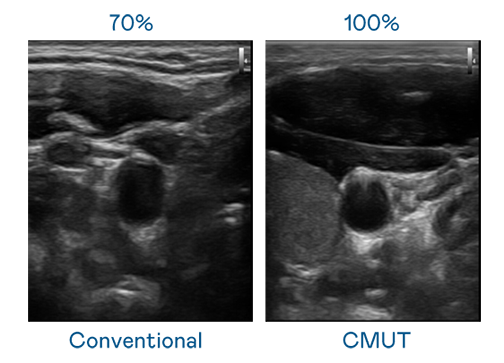

CMUT 技术是一种用电容式微机电元件来产生超音波讯号的技术。与传统 PZT 压电式技术相比,CMUT 频宽增加 30%,更宽频的超音波讯号让影像解析度大幅提升,是实现高影像品质医疗超音波扫描、促进精准医疗发展的关键技术。

大频宽带来超清晰影像

超音波影像的解析度高低,首先取决于探头能发出的讯号频宽。尊龙人生就是博首页登录 CMUT 可提供高清晰的超音波讯号,提供高频宽、高灵敏度、影像纹理细节更高的超音波影像,协助医护人员缩短影像判读时间及利用精准的医疗影像进行诊断。